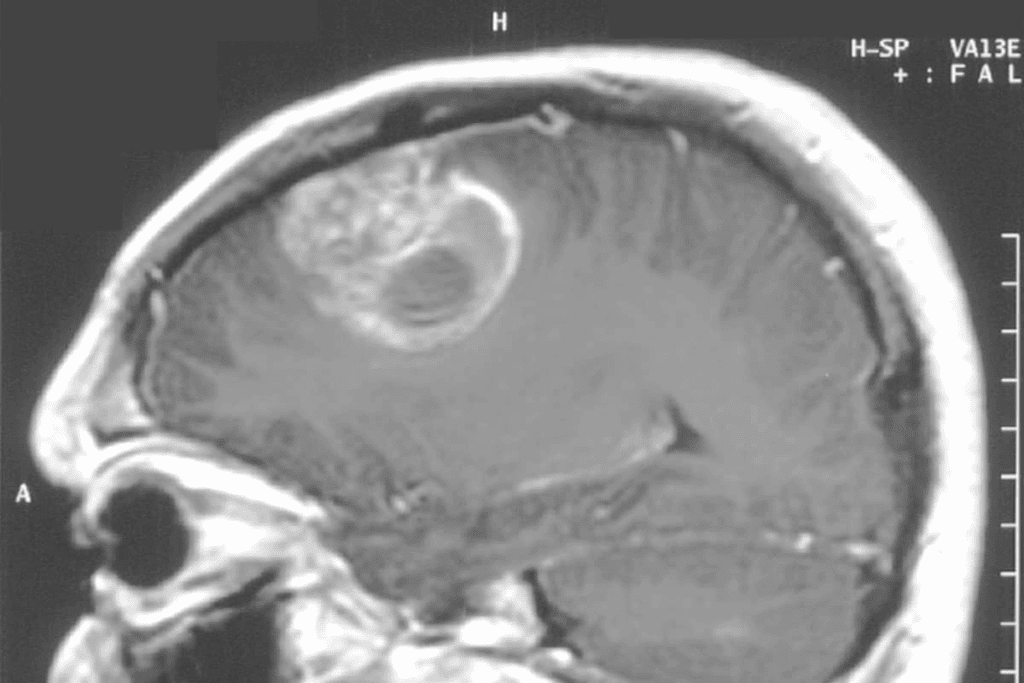

Neuroimaging and Brain Scans

Neuroimaging is vital for diagnosing brain tumors and ruling out other causes of symptoms. MRI and CT scans give us detailed brain images.

| Imaging Technique | Primary Use | Benefits |

| MRI | Detailed soft tissue imaging | High sensitivity for detecting tumors and structural abnormalities |

| CT Scan | Quick assessment of brain structures | Useful in emergency settings and for patients with certain metal implants |